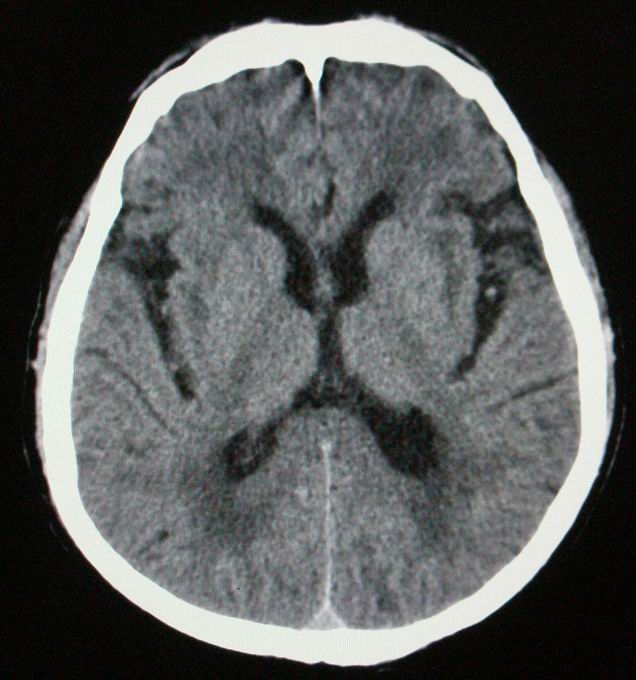

以下是引用随光逐影在2008-4-5 7:46:00的发言:[br]1)考虑为:多发性脑转移瘤。建议:行进一步检查。2)多发性腔隙性脑梗塞。3)脑白质病。4)脑萎缩。

以下是引用zjzjr在2008-4-5 9:00:00的发言:[br]1.双侧颞叶占位性病变,考虑为转移瘤可能性大。[br]2.左侧基底节区陈旧性腔隙性脑梗塞。[br]3.脑白质病。建议mri进一步检查。

以下是引用xuhuihong在2008-4-5 0:59:00的发言:[br]1.双侧颞叶占位性病变,考虑为转移瘤可能性大。[br]2.左侧基底节区陈旧性腔隙性脑梗塞。[br]3.脑白质病。建议mri进一步检查。

以下是引用形影不离在2008-4-4 23:29:00的发言:[br]1.双侧颞叶占位性病变,考虑为转移瘤可能性大。[br]2.左侧基底节区陈旧性腔隙性脑梗塞。[br]3.脑白质病。